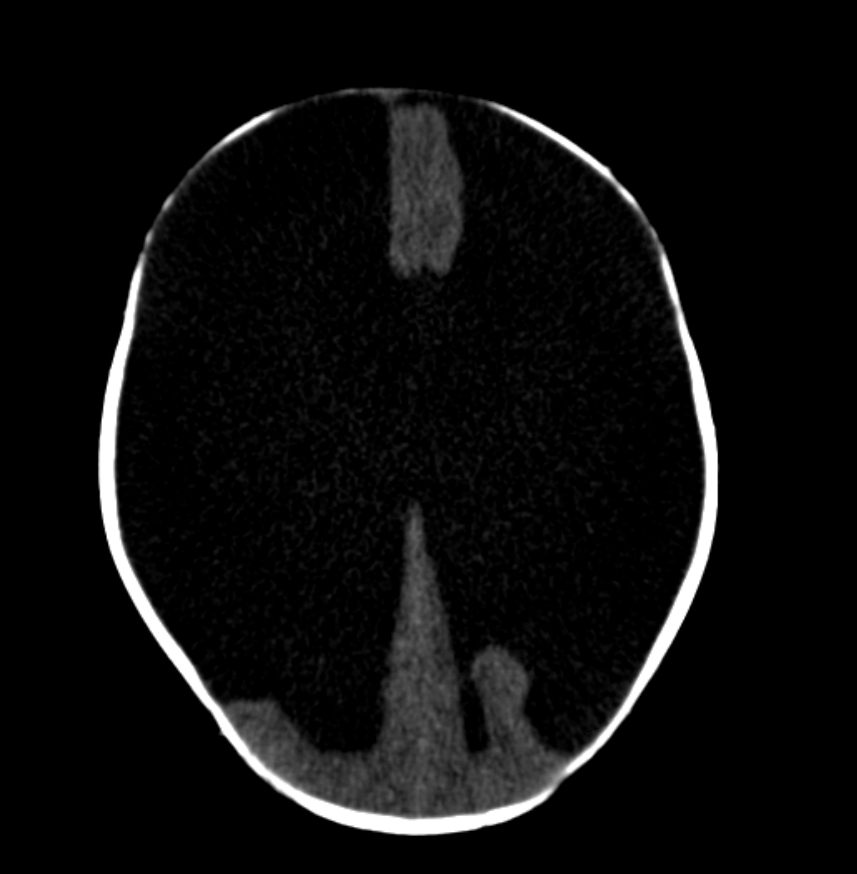

Hydranencephaly is a rare encephalopathy that occurs in-utero. It is characterised by destruction of the cerebral hemispheres which are transformed into a membranous sac containing cerebrospinal fluid and the remnants of cortex and white matter 1. Porencephaly is considered a less severe degree of the same pathology 10

There is marked enlargement of fluid spaces with little if any overlying cerebral parenchyma except for the posterior fossa and para medial location along the falx.

The posterior fossa structures are inferiorly displaced and the fourth ventricle is not well seen. Higher cuts demonstrate marked cerebral destruction of both cerebral hemispheres predominately in the distribution mid cerebral arteries with minimal residual tissue identified both anteriorly and posteriorly. The anterior fontanelle is bulging.

This case demonstrates typical CT and ultrasound appearances of hydranencephaly, which is in almost all cases not compatible with significant post natal survival.